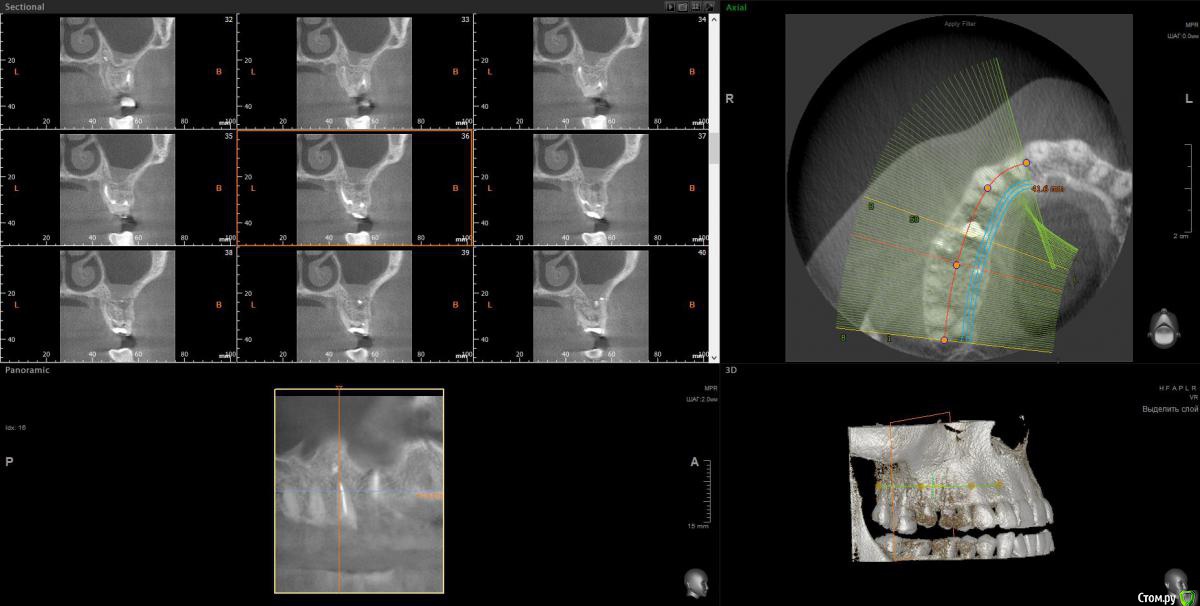

wladdX Опубликовано 2 февраля, 2017 Поделиться Опубликовано 2 февраля, 2017 Несколько скриншотов на скорую руку. Ссылка на комментарий

Весна2009 Опубликовано 2 февраля, 2017 Автор Поделиться Опубликовано 2 февраля, 2017 Несколько скриншотов на скорую руку.Огромное Вам спасибо! Может быть, есть желающие прокомментировать снимки? Заранее спасибо Ссылка на комментарий

Весна2009 Опубликовано 30 января, 2017 Автор Поделиться Опубликовано 30 января, 2017 Размер пришлось уменьшить,н е загружалось, качество стало хуже Ссылка на комментарий